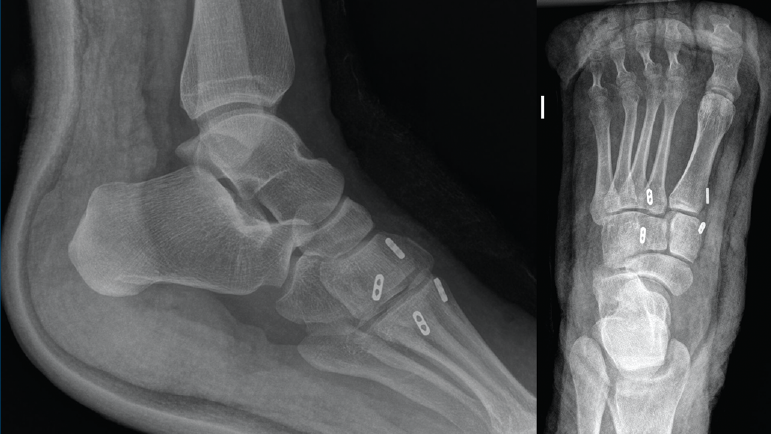

Se realiza cirugía con 2 suturas intraóseas C1-M2 y C2-M1 mediante la técnica descrita anteriormente (Figura 4). Se siguió un protocolo posquirúrgico igual al del caso anterior: revisión de la herida a los 10 días, descarga hasta las 6 semanas, carga parcial hasta las 8 semanas con bota y comenzar la carga completa con calzado cómodo con plantilla con soporte de arco longitudinal interno hasta un año postoperatorio.

Figura 4. Caso 2. Radiografías lateral y anteroposterior sin carga de control tras la cirugía con fijación no rígida.

La revisión a los 3 meses mostró resultados satisfactorios en ambos casos, con tolerancia de la carga completa. Además, las imágenes radiológicas demostraron el mantenimiento de la reducción conseguida en el quirófano, sin movilización del material (Figuras 5 y 6).

Figura 5. Resultados radiográficos posquirúrgicos en el caso 1.

En el primer caso, la incorporación laboral fue a los 4 meses y, en el segundo caso, a los 6 meses; los pacientes no presentaron dolor. A los 10 meses postoperatorios el examen clínico no reveló evidencia de dolor en la zona quirúrgica y los pacientes habían reanudado todas sus actividades regulares, incluida la práctica deportiva, sin complicaciones. Además, las radiografías en ese momento revelaron una reducción anatómica de la lesión.

Figura 6. Resultados radiográficos posquirúrgicos en el caso 2.